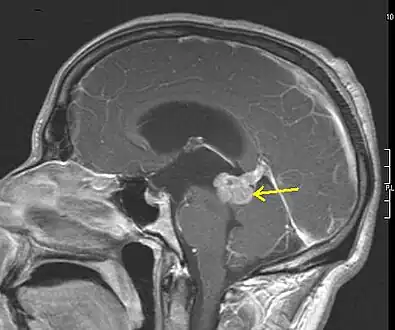

-

Low grade astrocytoma of the midbrain (lamina tecti), sagittal T1-weighted magnetic resonance imaging after contrast medium administration: The tumor is marked with an arrow. The CSF spaces in front of the tumor are expanded due to compression-induced hydrocephalus internus. -